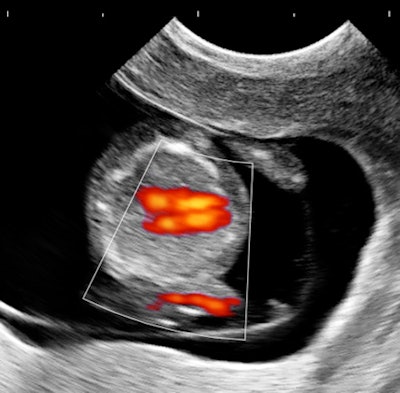

Case 1: Pregnancy, day 64

My own private practice has some routine scanning from local physicians and second-opinion scanning from a much wider geographic zone. Most of the "abnormal NT" cases I used to see were just normal embryos resting supine on the amnion. A recent case was referred from an infertility practice: an 11.2-week embryo thought to have an abnormal NT. This embryo, having a higher specific gravity than amniotic fluid, was dependent in the sac, resting on amnion. Here are an endovaginal view of the neck, an energy Doppler view of the heart, and a 3D survey:

All images courtesy of Dr. Jason Birnholz.

There are multiple cystic hygromas and an apparently normal heart. The 3D really does not look "right" because of a disproportion. No other abnormal findings were evident. We did a cell-free fetal DNA test on maternal blood that established in a few days that this is a case of Trisomy 18.